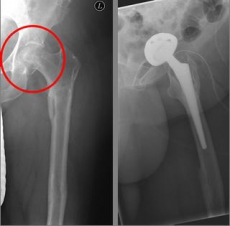

Picture: This picture shows the treatment of a severely displaced fracture with a so-called duo head prosthesis. The acetabulum was left here.

Picture: In this case, there was already a wear of the hip joint and the affected patient was relatively young, so that a cement-free total endoprosthesis (TEP) of the hip was selected for the treatment of the femoral neck fracture. Here, in addition to the femoral head, the acetabular cup was replaced by an implant.